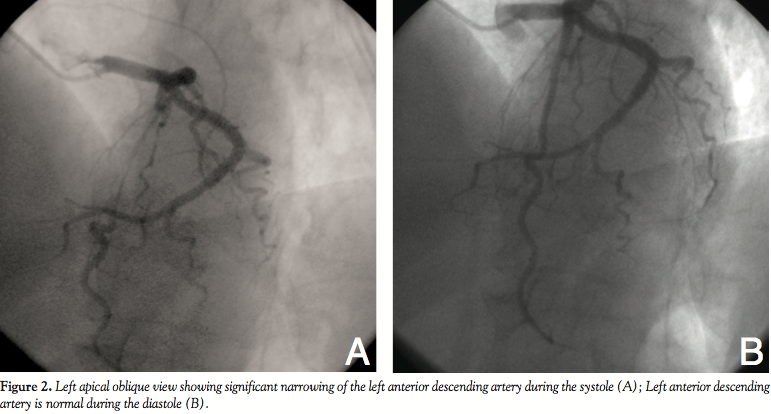

Case Report 1. A 51-year-old woman was admitted to the cardiology clinic because of loss of consciousness. She had no previous history of disease. She described presyncope occurring approximately 1 year prior. The present syncope lasted 1-2 minutes and there were no epileptic attacks or incontinence. Physical examination on admission was unremarkable. Blood pressure levels were also normal. Twelve-lead electrocardiogram revealed sinus bradycardia (32 bpm) (Figure 1). After 1 mg of atropine, heart rate quickened (136 bpm). Transthoracic echocardiography revealed normal systolic and diastolic functions. We performed 24 hour Holter monitoring which demonstrated tachycardia-bradycardia attacks. In addition, there were sinus pauses lasting more than 3 seconds during daily Holter monitoring. Because of suspicion of sick sinus syndrome, we performed an electrophysiology study. Sinus node dysfunction was detected. We also performed coronary angiography because of intermittent chest pains and there

were no significant lesions. Only myocardial bridge (MB) in the left ascending coronary artery (LAD) causing significant stenosis was demonstrated (Figures 2A and 2B). A permanent pacemaker (dual-chamber) was implanted because of symptomatic sinus bradycardia. She was discharged on the fifth day of admission.